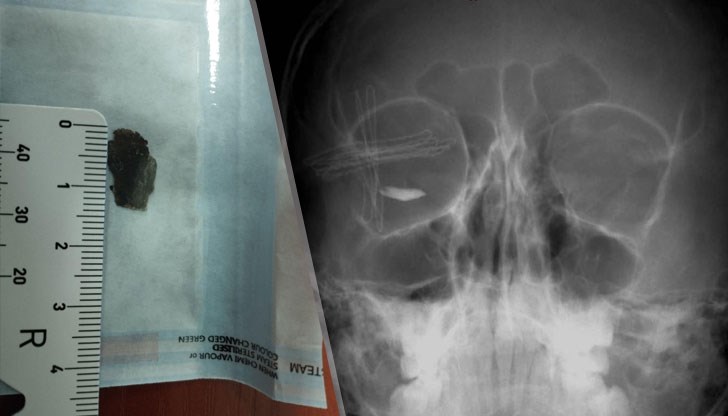

Метално чуждо тяло с размер 15 мм проникна в окото на детето при цепене на дърва

Лекарски екип от УМБАЛ "Александровска" в София извърши успешна спешна операция на 11-годишно дете със сериозна разкъсно-контузна травма на дясното око, получена при цепене на дърва. По време на интервенцията бе отстранено метално чуждо тяло с размер близо 15 мм, съобщи проф. Александър Оскар във Фейсбук.

Състоянието на детето преди операцията е било тежко – със силно намалено зрение, хипотония на окото, разкъсни рани на клепач и склера, наличие на хифема и фибрин в предната камера.